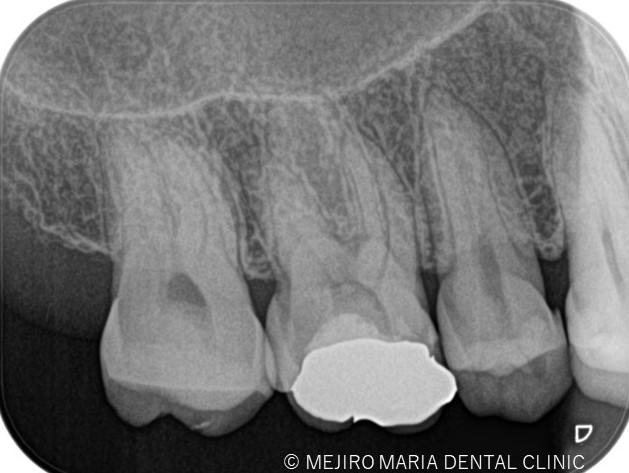

今回は術前に歯髄炎による疼痛を確認していたため、水酸化カルシウムを貼薬した後、2回目の治療にて根管充填、支台築造処置を終了させている。

治療後の様子

次週、問題なければ仮歯の作製および、最終補綴物の製作に移行する。

3ヶ月後に経過観察を行い最終的な根管治療の予後を確認する予定。